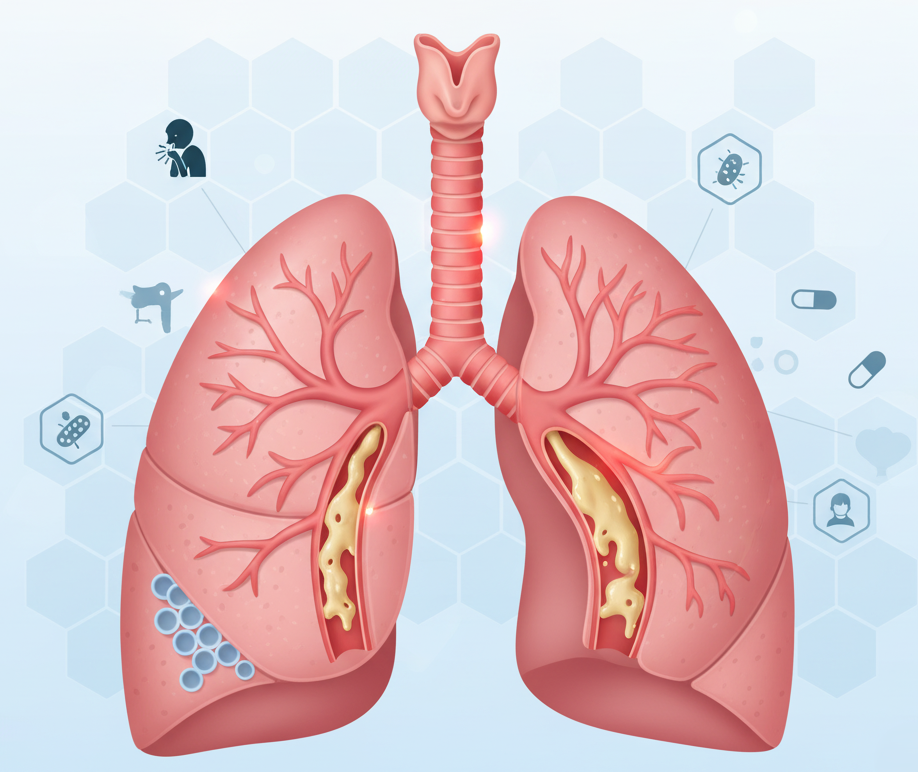

Bronchitis: A Complete Guide for the Symptom, Cause, and Treatment

One of the most common respiratory conditions that affects millions of people worldwide, this guide…